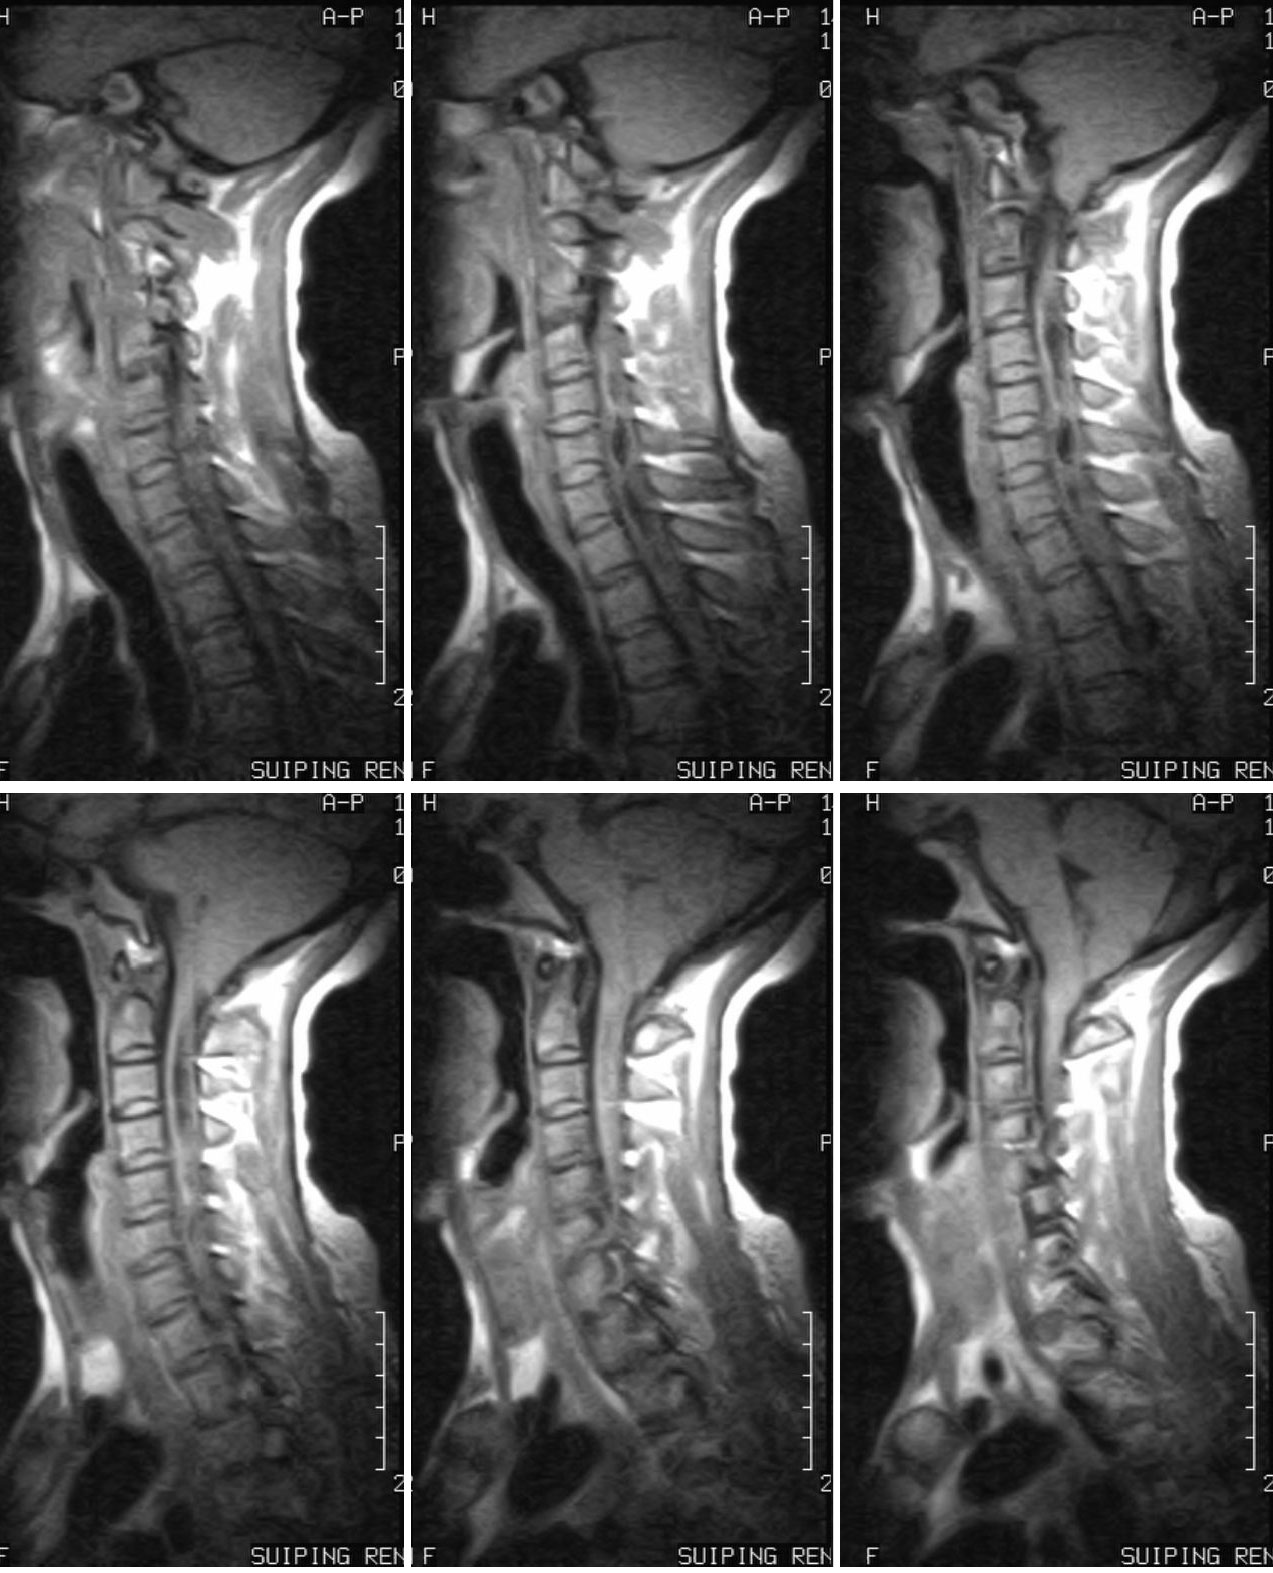

CHiari 畸形并脊髓空洞

女 46岁 因颈部不适,按颈椎病治疗无效。

本例楼主没有公布结果,大家一致的意见为:CHiari 畸形并脊髓空洞。